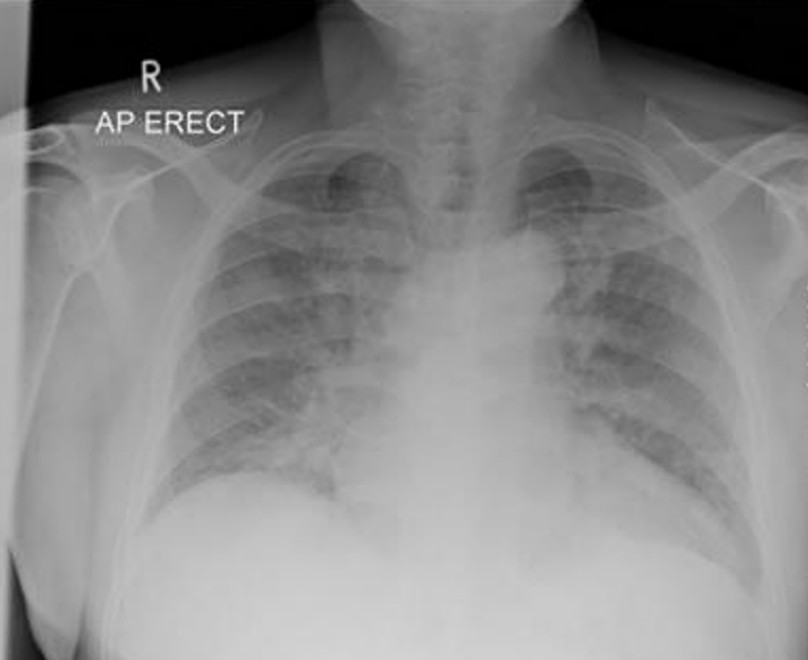

A CXR was obtained.

3. Give (2) salient findings from the chest xray and your interpretation 3 marks